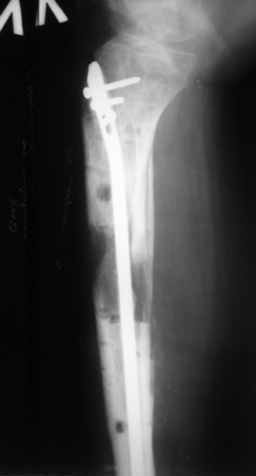

Ерсин, мы тоже имеем опыт такой фиксации. Подобную операцию за последние 3 года мы сделали трем пациентам. Снимки одного из них я прилагаю. К сожалению, ни в одном из этих 3-х случаев мы не получили удовлетворяющего нас результата. Очень трудно провести штифт, введенный антеградно ровно по центру таранной кости. Отсутствие подвижности между диафизом и дистальным отломком большеберцовой кости (после фиксации в аппарате в течение 1-2 мес) очень усложняет проведение штифта в центр блока таранной кости. Поэтому мы от этого пока отказались, и проводим штифт через пятку. При данном варианте фиксации подобных проблем не возникало ни разу.

Вложение не в текстовом формате было извлечено…

Имя     : 2.jpg

Тип     : image/jpeg

Размер  : 16416 байтов

Описание: отсутствует

Url     : http://weborto.net:8080/pipermail/ortho/attachments/20081209/5d3bc875/attachment-0005.jpg